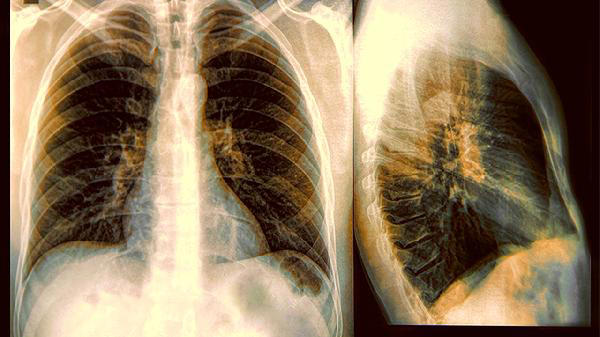

Ai có thể ngờ một người đàn ông trung niên sống điều độ, không thuốc lá, không rượu bia, lại nhận kết quả khám sức khỏe với 4 chữ ''ung thư phổi giai đoạn cuối''?

Theo Tổ chức Y tế Thế giới (WHO), khoảng 10 đến 20% bệnh nhân ung thư phổi trên thế giới là người không hút thuốc. Nguyên nhân có thể liên quan đến ô nhiễm không khí trong nhà, khí radon, khói bếp, yếu tố nghề nghiệp hoặc thói quen sinh hoạt kéo dài nhiều năm.

Trường hợp người đàn ông nói trên cho thấy những yếu tố ban đêm cũng có thể đóng vai trò đáng kể.